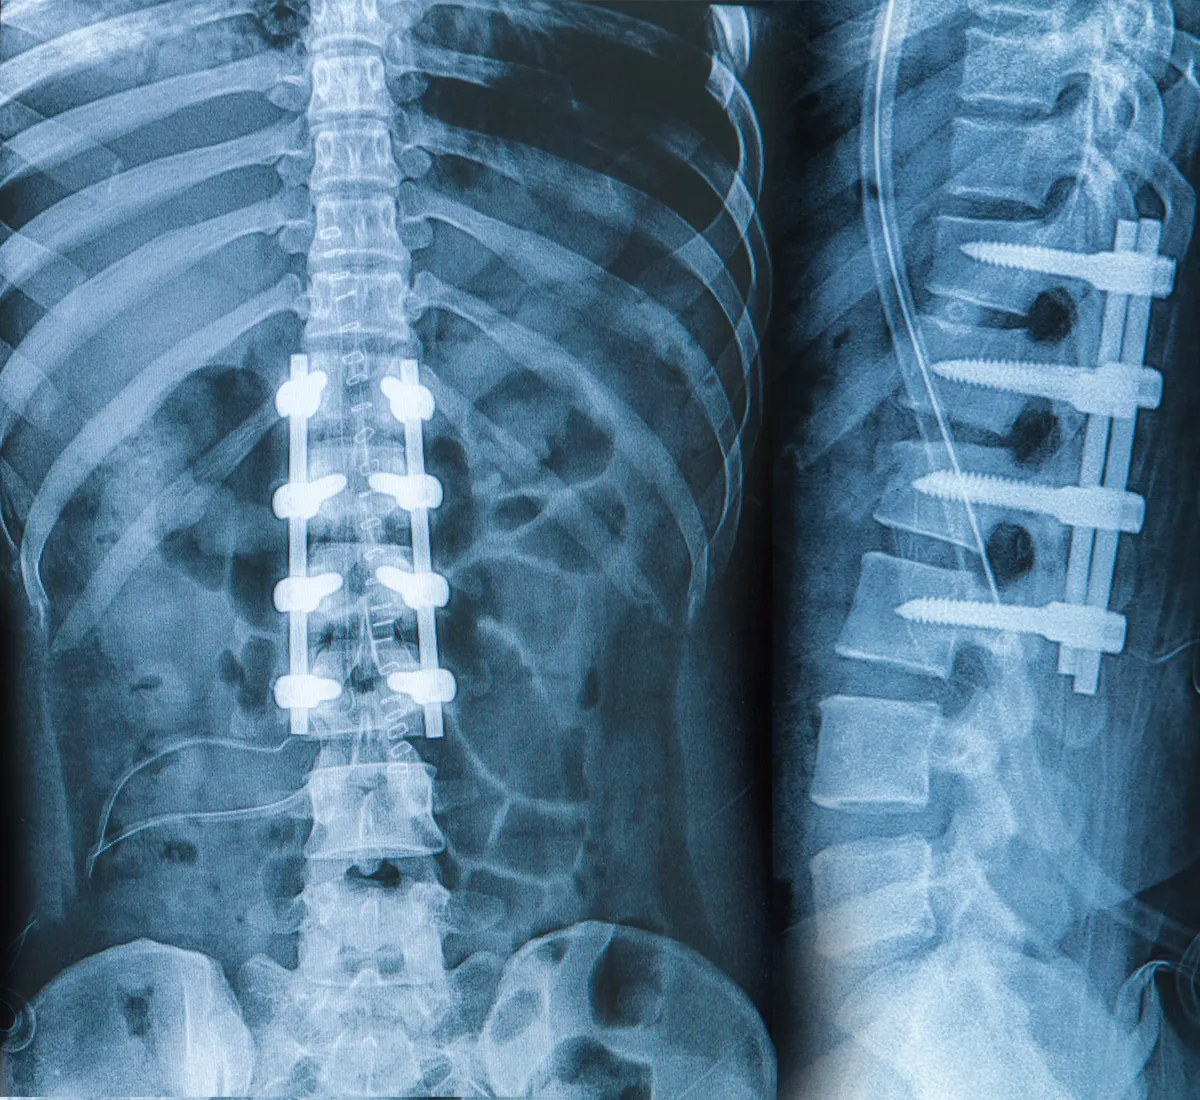

Spinal fusion is a surgical procedure to reduce or stop the movement of the spine. This process is performed by joining two or more bones of the spine. Surgery can be performed to treat conditions such as spinal deformities, instability, and disc herniation. Fusion is achieved by fusing the bones, and this process can often take up to a year. Patients often experience a significant reduction in pain and an increase in quality of life after surgery. Spine Fusion is a sensible surgery for patients who suffer from pain.